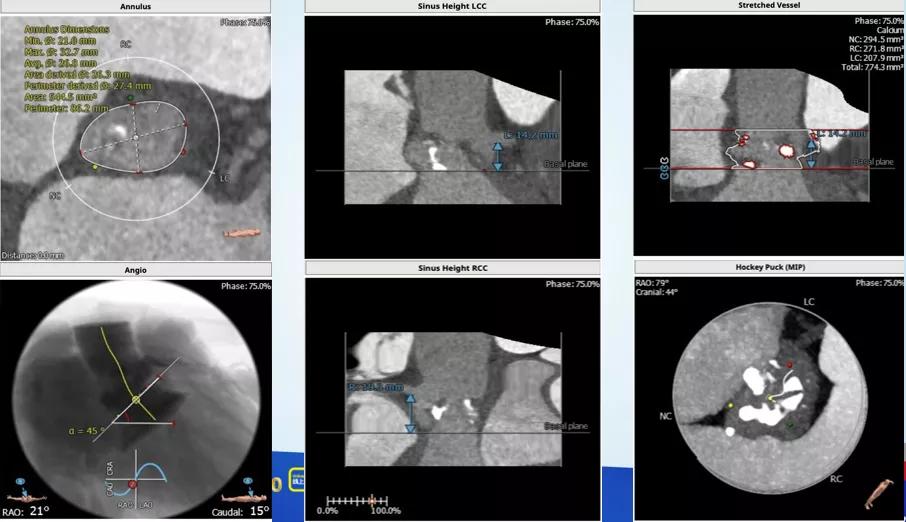

这个病人从超声看,是一个以反流为主的病例,狭窄只是中度,左室已经70。从CT分析看,瓣环-流出道呈开放性,左右冠瓣可疑融合,左冠高度虽然有14,但是左冠瓣叶很长,增厚,提示有冠脉风险。导丝刚跨瓣,病人就出现室颤,经药物调整后暂时稳定,25的球囊预扩后发现左冠完全不显影,而且患者再次反复室颤,此时为了稳定循环,第二因为冠脉风险,决定先从左侧股动静脉上ECMO保护。

根部解剖:

置入Venus-A32号瓣膜并释放